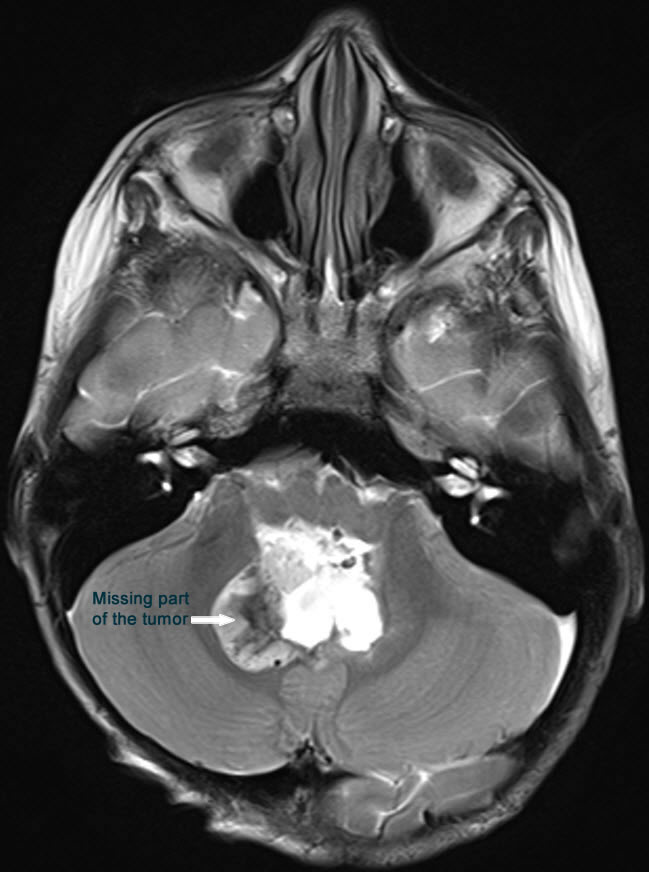

Midline posterior occipital approach in setting position. The bone flap reflected to the neck inferior. The dura was opened in V-shape fashion. The tonsils were shifted downward and the vermis is prominent by the tumor. Sharp dissection of the inferior pole of the vermis ( The uvula). The tumor was highly vascular with rich blood supply. The tumor was coagulated sucked and most of the upper part was removed. The inferior part was was removed until the obex with related structures were seen. The left part of the tumor was followed and resected until the foramen of Leuschko was seen and the left inferior cerebellar peduncle was preserved. The same maneuver was undertaken in the right side. The tumor inside the 4th ventricle was removed and the floor of the 4th ventricle was seen intact with widened aqueduct through which the third ventricle was seen. The superior medullary velum was respected. The floor of the 4th ventricle was flattened due to the previous compression effect of the tumor, that it was impossible to see the median sulcus, nor the paramedian sulci limitantes or the hypoglossal trigone elevations at the calamis scriptorius. I got the impression that the tumor was totally resected, for what intraoperative MRI control with contrast was done.

Fig-35: transfer to MRI for first check up.

Fig-36: MRI done during surgery showing the missing part of the tumor, which was subsequently removed.

There is still part of the tumor in the right upper corner and the right foramen of Leuschko. Resection of this part was achieved until the normal cerebellar tissues were seen at these angles. Strict hemostasis with water-tight closure of the dura and bone flap was secured with 2 stitches and routine closure of the wound.